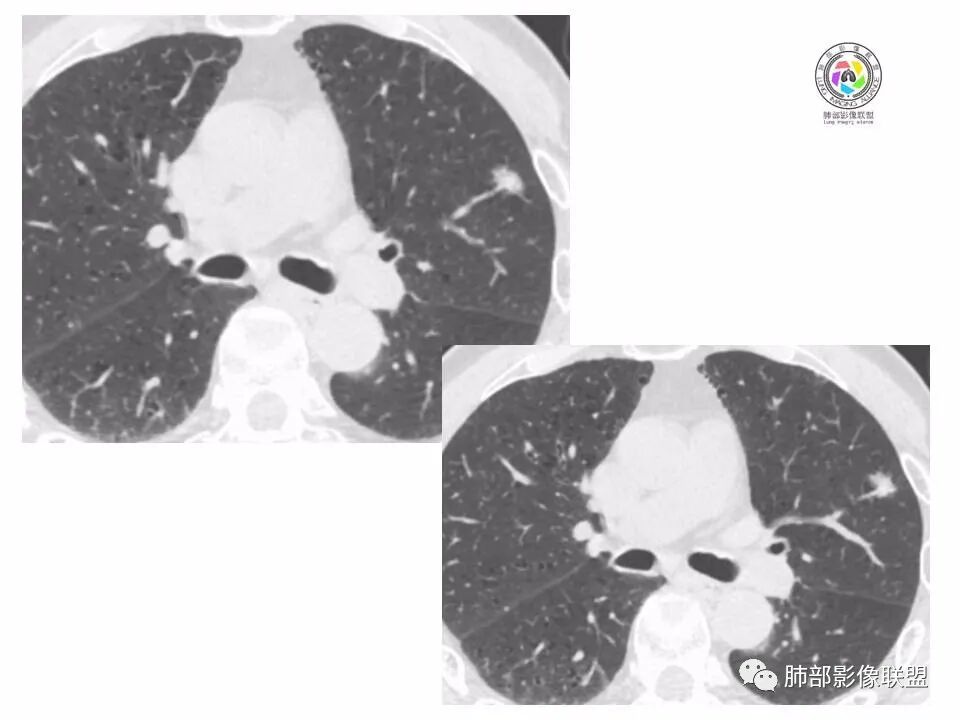

左肺上叶小结节,边缘毛糙,血管集束,支气管截断,强化较明显,但U型凹陷,部分边缘平直,总体感觉恶性大于良性,首选腺癌,鉴别炎性肉芽肿。

左上肺结节,月牙征,边缘纠集有收缩力,小空泡,血管增粗进入,纵隔淋巴结增大,考虑恶性,隐球菌待排。

老年男性,左上肺结节,边缘毛糙,临近血管进入增粗,内部隐约可见小空泡或远端扩张支气管,血管集束并伴月牙铲,有个横断界面看似像脐凹征,常规考虑腺癌,鉴别隐球。

结节,分叶,边缘毛糙,小空泡,血管集束并伴月牙铲,有强化,老年男性,考虑腺癌,建议复查除外结核。

左肺上叶混合密度结节,边缘见边缘清楚磨玻璃,分叶,U型凹陷,首先考虑腺癌。

左肺上叶结节影,边缘可见分叶,血管集束及月牙铲征,病灶内见小空泡影,考虑腺癌可能。

结节密度不均匀,混合磨玻璃结节,大部分实性部分,边缘清,月牙铲征,肿瘤微血管征,考虑肺癌。

老年男性,体检发现左肺上叶结节,周围浅分叶伴磨玻璃影,有血管相连,U型凹陷,纵隔见肿大淋巴结,考虑为恶性,腺癌可能。

左肺形态不规则结节,边缘收缩,毛刺,有月牙铲,纵隔窗比肺窗小,不密实,近段血管与病灶相连,强化不明显,老年男性,综合考虑,恶性,腺癌,鉴别炎性结节。建议穿刺。

老年男性,左肺上叶结节,边界清,不规则,有毛刺,血管集束,空泡,边缘有气肿带,考虑腺癌,鉴别肉芽肿。

左肺上叶小结节,边缘毛糙,血管集束,支气管截断,有月牙铲,首选腺癌,鉴别炎性肉芽肿。

左上肺实性小结节,短毛刺,月牙铲,似见小空泡,血管集束,有轻度强化,首先考虑腺癌。

老年男性,肺气肿背景,左肺上叶小结节,大部分边缘平直,部分边缘膨隆,局部可见月牙铲,边缘少许磨玻璃,边界清晰,血管进入,轻度强化,首先考虑腺癌,常规抗炎后复查,除外炎性结节。

左上肺结节,短毛刺,空泡,月牙铲,脐凹征,考虑腺癌。

左肺上叶混合密度结节,边界清,分叶,毛刺,血管进入,月牙铲,有强化,首先考虑腺癌,有平直边,收缩力不明显,常规先抗炎。

左上肺结节分叶,边缘毛糙,小空泡可能,血管集束,月牙,纵隔窗面积小于肺窗,有磨玻璃成份,有强化,老年男性,白细胞高,恶性的征象都有,但磨玻璃的形态和边界不好评估,实性为主,看形态和边缘局部较散缺乏饱满感,顶着压力反着来猜炎性可能大。复查不消失会考虑腺癌或黏液腺癌。

老年男性,肺气肿背景,左肺上叶实性结节,边界清,边缘平直为主,细长毛刺,较明显强化,考虑炎性病灶,隐球?

老年男性,左肺上叶结节,边缘可见长毛刺、较软,并可见分叶,周围可见清楚磨玻璃密度,内可见空泡征,增强后呈均匀强化,良恶性征象都有,感觉收缩力不强,化验白细胞偏高,建议抗炎治疗后复查除外腺癌。

老年男性,左肺上叶混合密度结节,空泡,分叶,血管集束,有强化,考虑腺癌;细长软毛刺,血管走行自然,边缘有平直收缩,白细胞高,肿标正常,考虑炎性结节。猜炎性结节,鉴别腺癌。

左肺上叶前段mGGN,边缘见毛刺及月牙铲,考虑腺癌,需要薄层图像确认所见征象。

左肺上叶结节,分叶,边缘毛糙,小空泡,月牙铲,有强化,考虑浸润性腺癌,鉴别炎性肉芽肿。

患者老年男性,体检发现。查癌胚抗原不高。血常规血象升高。胸部CT:肺气肿背景,左肺上叶近胸膜下实性结节,边缘光滑,边界清楚,可见毛刺、血管集束、月牙铲征象,增强不明显,内可见低密度区,综合考虑恶性病变,腺癌可能大,鉴别结核及炎性结节。

老年男性,左肺上叶结节,周围浅分叶伴磨玻璃影,有血管相连,月牙铲。纵隔见肿大淋巴结,但白细胞高。腺癌首先,需排除炎性假瘤。抗炎治疗后复查。

老年男性,体检发现左肺结节,分叶、脐凹、月牙铲及月牙铲附近有边缘清楚的磨玻璃影,上述征像均指向恶性肿瘤,有疑问的地方:毛刺软无力,无胸膜牵拉及白细胞计数升高。整体是腺癌,需要抗议后复查以排除炎性病变。

图片有限,左肺上叶结节病灶,有张力,有收缩及小泡征,边缘可见月牙征,周围长毛刺及血管集束征,增强目测有中度以上强化,首先考虑恶性病变,腺癌。

左肺上叶前段小结节,边缘稍毛糙,月牙铲,血管进入可疑脐凹征,小空泡?增强有强化,老年男性,要高度警惕腺癌,但感觉毛刺偏细软,周围磨玻璃不明显,常规查隐球菌荚膜抗原除外隐球菌,血象高,抗炎后短期复查除外炎性结节。

左肺上叶mGGN,边缘收缩平直为主,肺窗显示清楚,纵隔窗体积缩小,未见胸膜牵拉,倾向感染性结节,隔期复查。